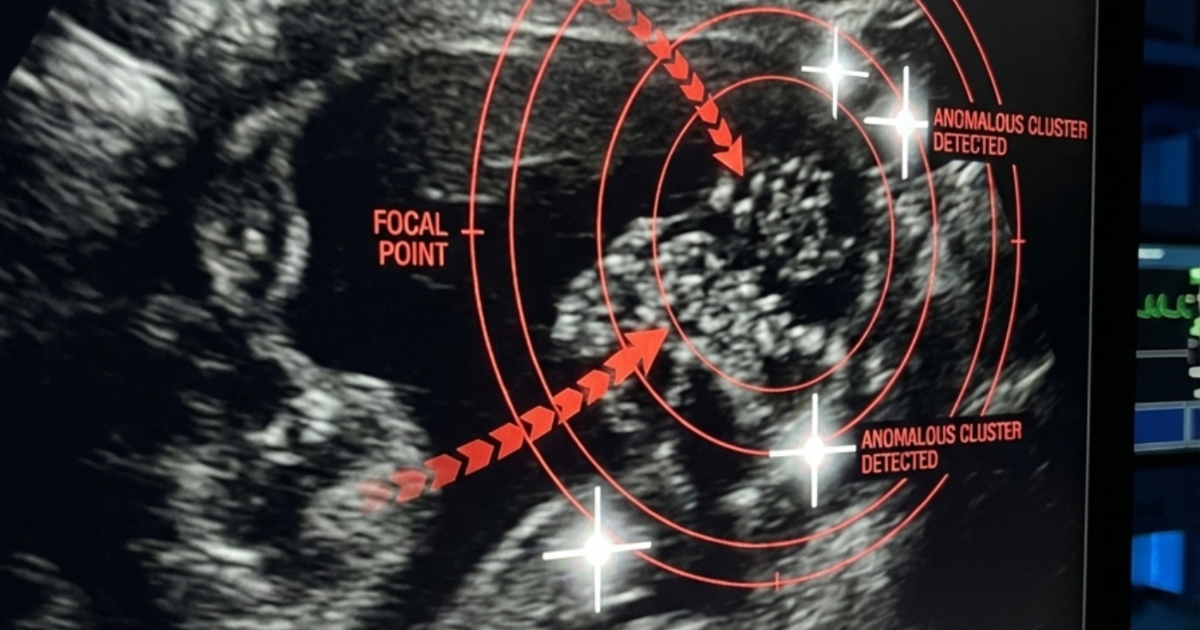

В приёмном отделении время будто остановилось. Моя дочь лежала на каталке, сжимаясь от боли, пока врачи срочно проводили УЗИ. Мы ждали, не находя себе места, ловя каждый взгляд медиков. И вот к нам подошёл врач и произнёс слова, от которых у меня подкосились ноги: «Нужна срочная операция». Оказалось, что все эти месяцы боль в спине была вызвана не усталостью, а растущим камнем в почке, о котором мы даже не подозревали. В тот день он сместился и перекрыл проток, вызвав сильнейшую боль и серьёзную угрозу для её здоровья.